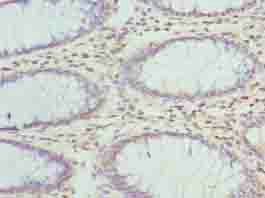

ApplicationELISA, IHC; Recommended dilution: IHC:1:20-1:200